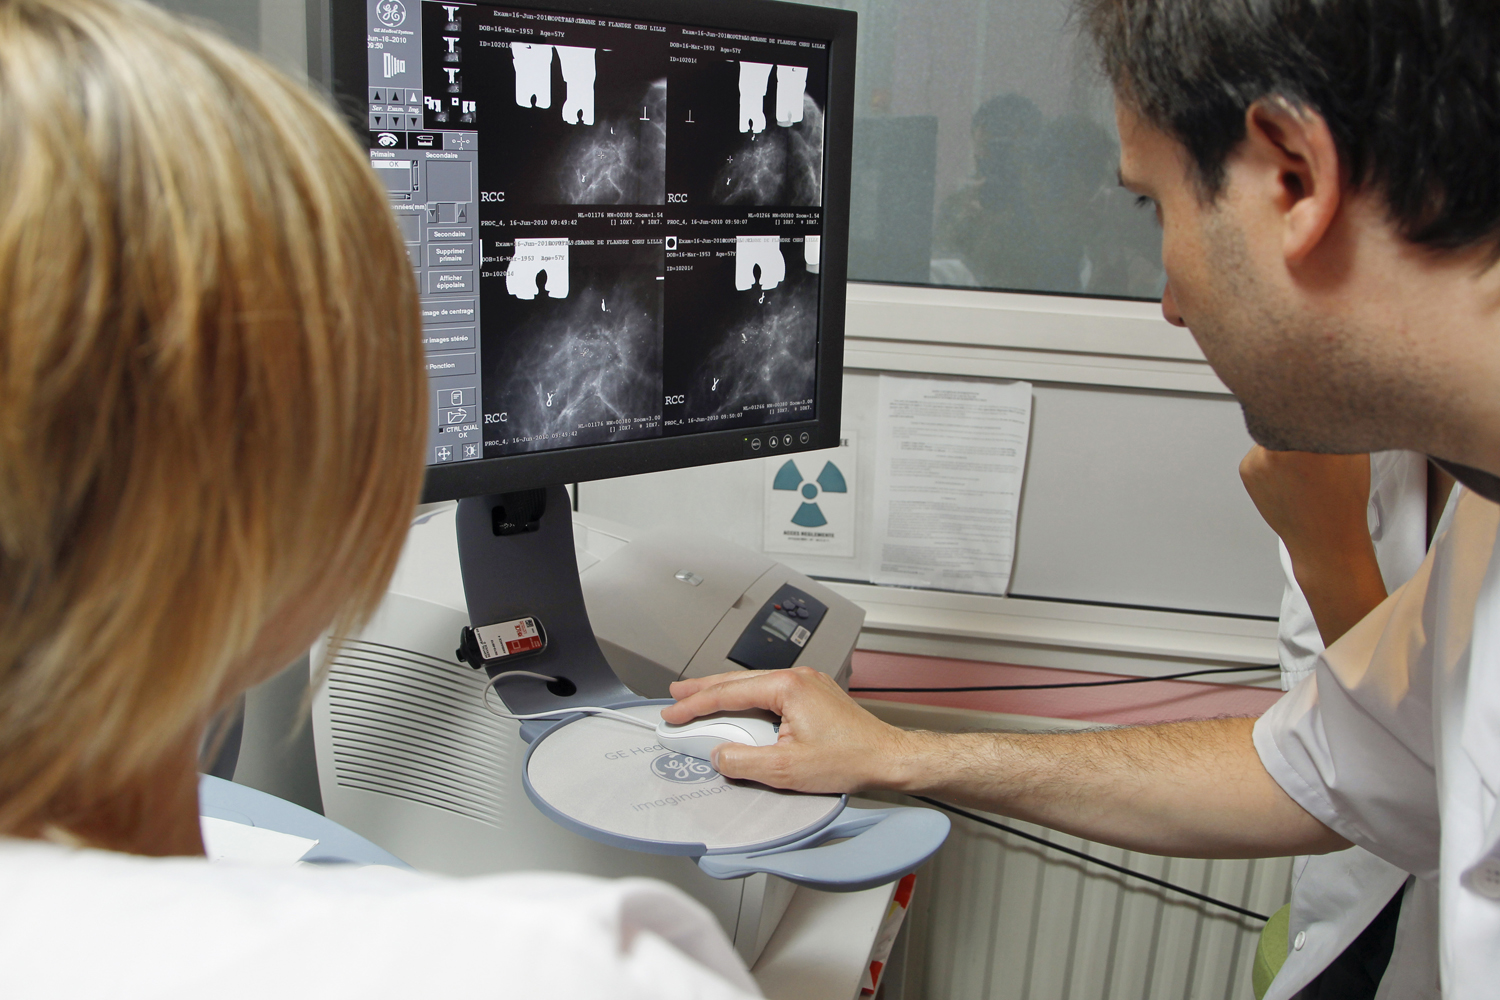

7. Nem veszélyes ez a vizsgálat?

Na, ez nehéz kérdés. Az utóbbi években sok tanulmány jelent meg, melyekben azt állítják, hogy mivel a mammográfia során röntgenfelvételt készítenek a mellről, az évenkénti rendszeres szűrés felesleges sugárterhelésnek teszi ki a szervezetet, és okosabb lenne ultrahangos vizsgálattal, szakember által végzett áttapogatással kiváltani ezt. Mások azonban azt mondják, hogy a mammográfia haszna jóval nagyobb, mint a kockázata, mert egészen apró, más módszerekkel észrevehetetlen elváltozásokat is ki tud mutatni, és rengeteg nő életét menti meg a korai diagnózis.